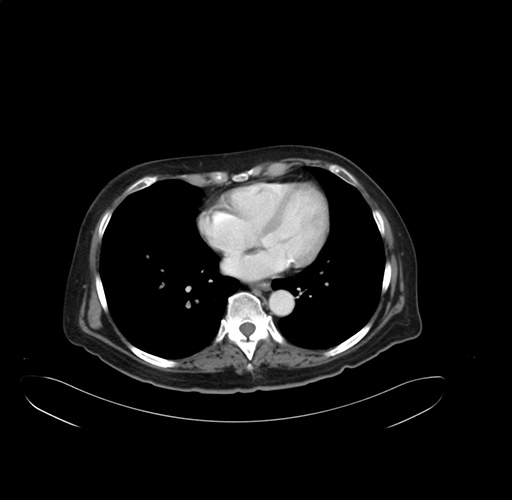

Axial Venous